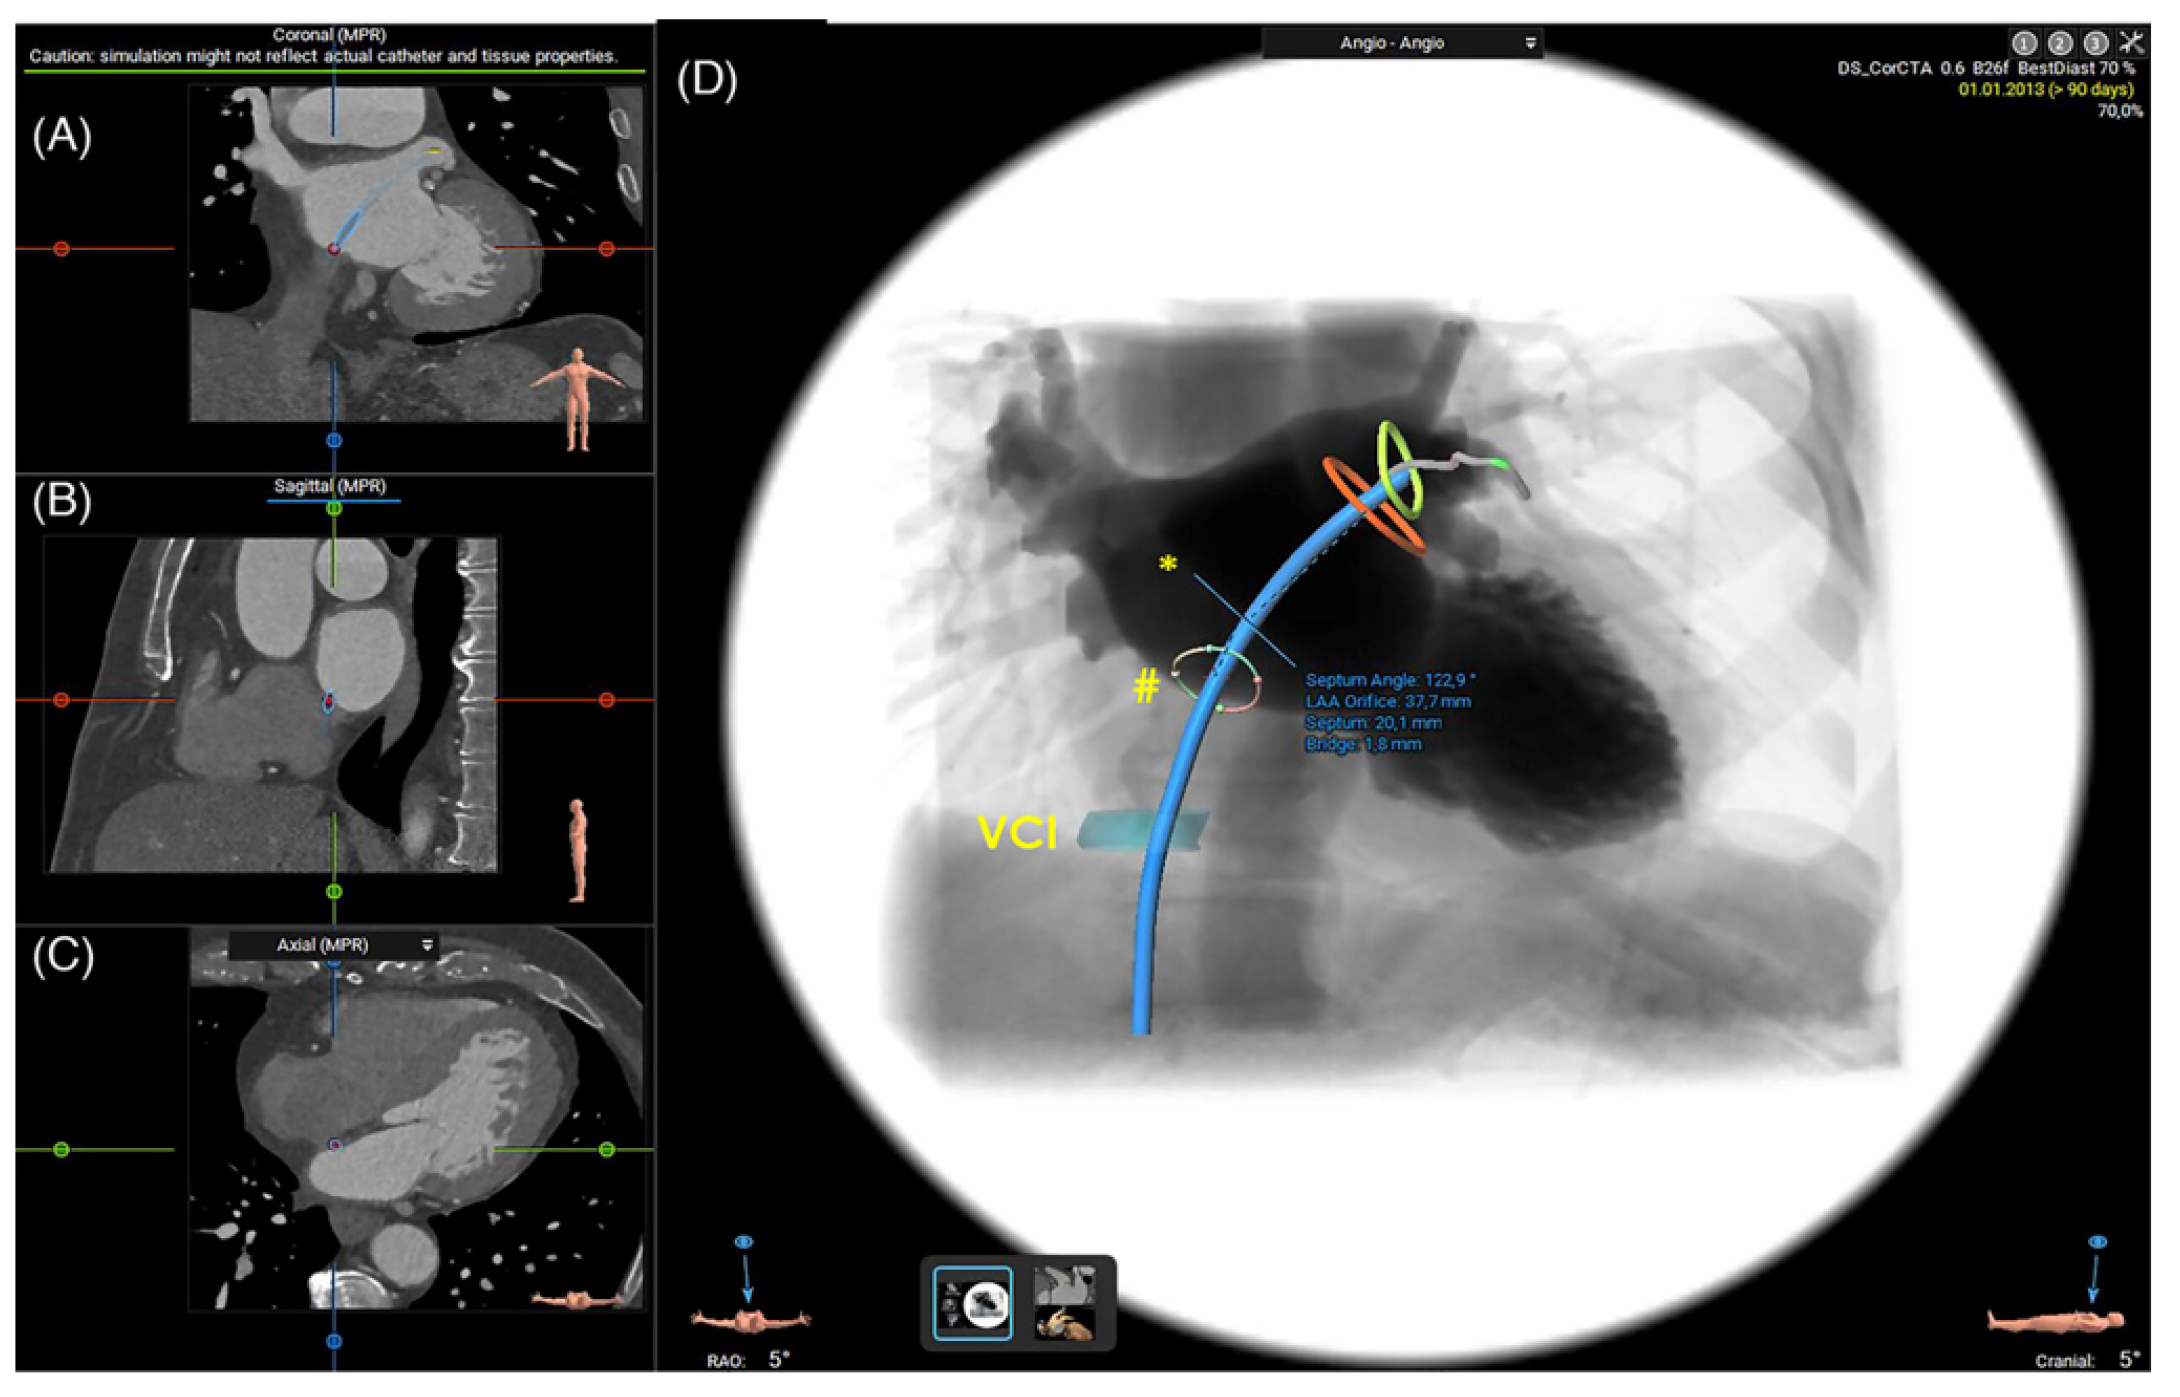

2.1.3. Assessment of the Inter-Atrial Septum

2.1.5. 3D Printing and Virtual Reality